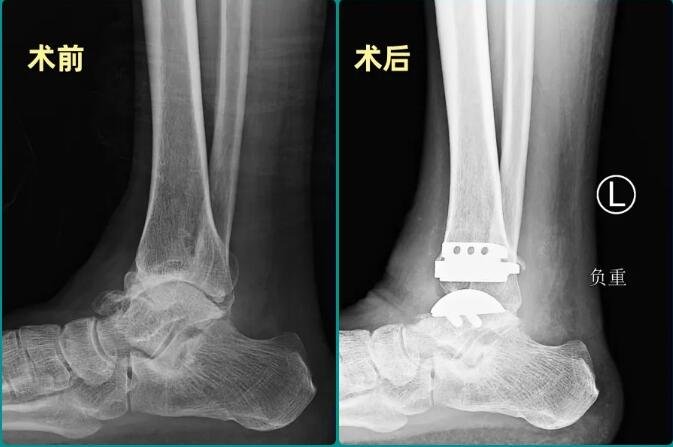

△赵大爷左踝手术前后X光对比。

听说betway在线登陆足踝外科有着成熟的人工全踝关节置换技术,赵大爷于2023年初慕名前来。betway在线登陆副院长、足踝大科主任石荣剑率领团队认真研判病情后,认为赵大爷具备全踝关节置换的条件。借助3D打印导板等数字化技术辅助,sararz足踝团队为赵大爷实施了人工全踝关节置换手术。